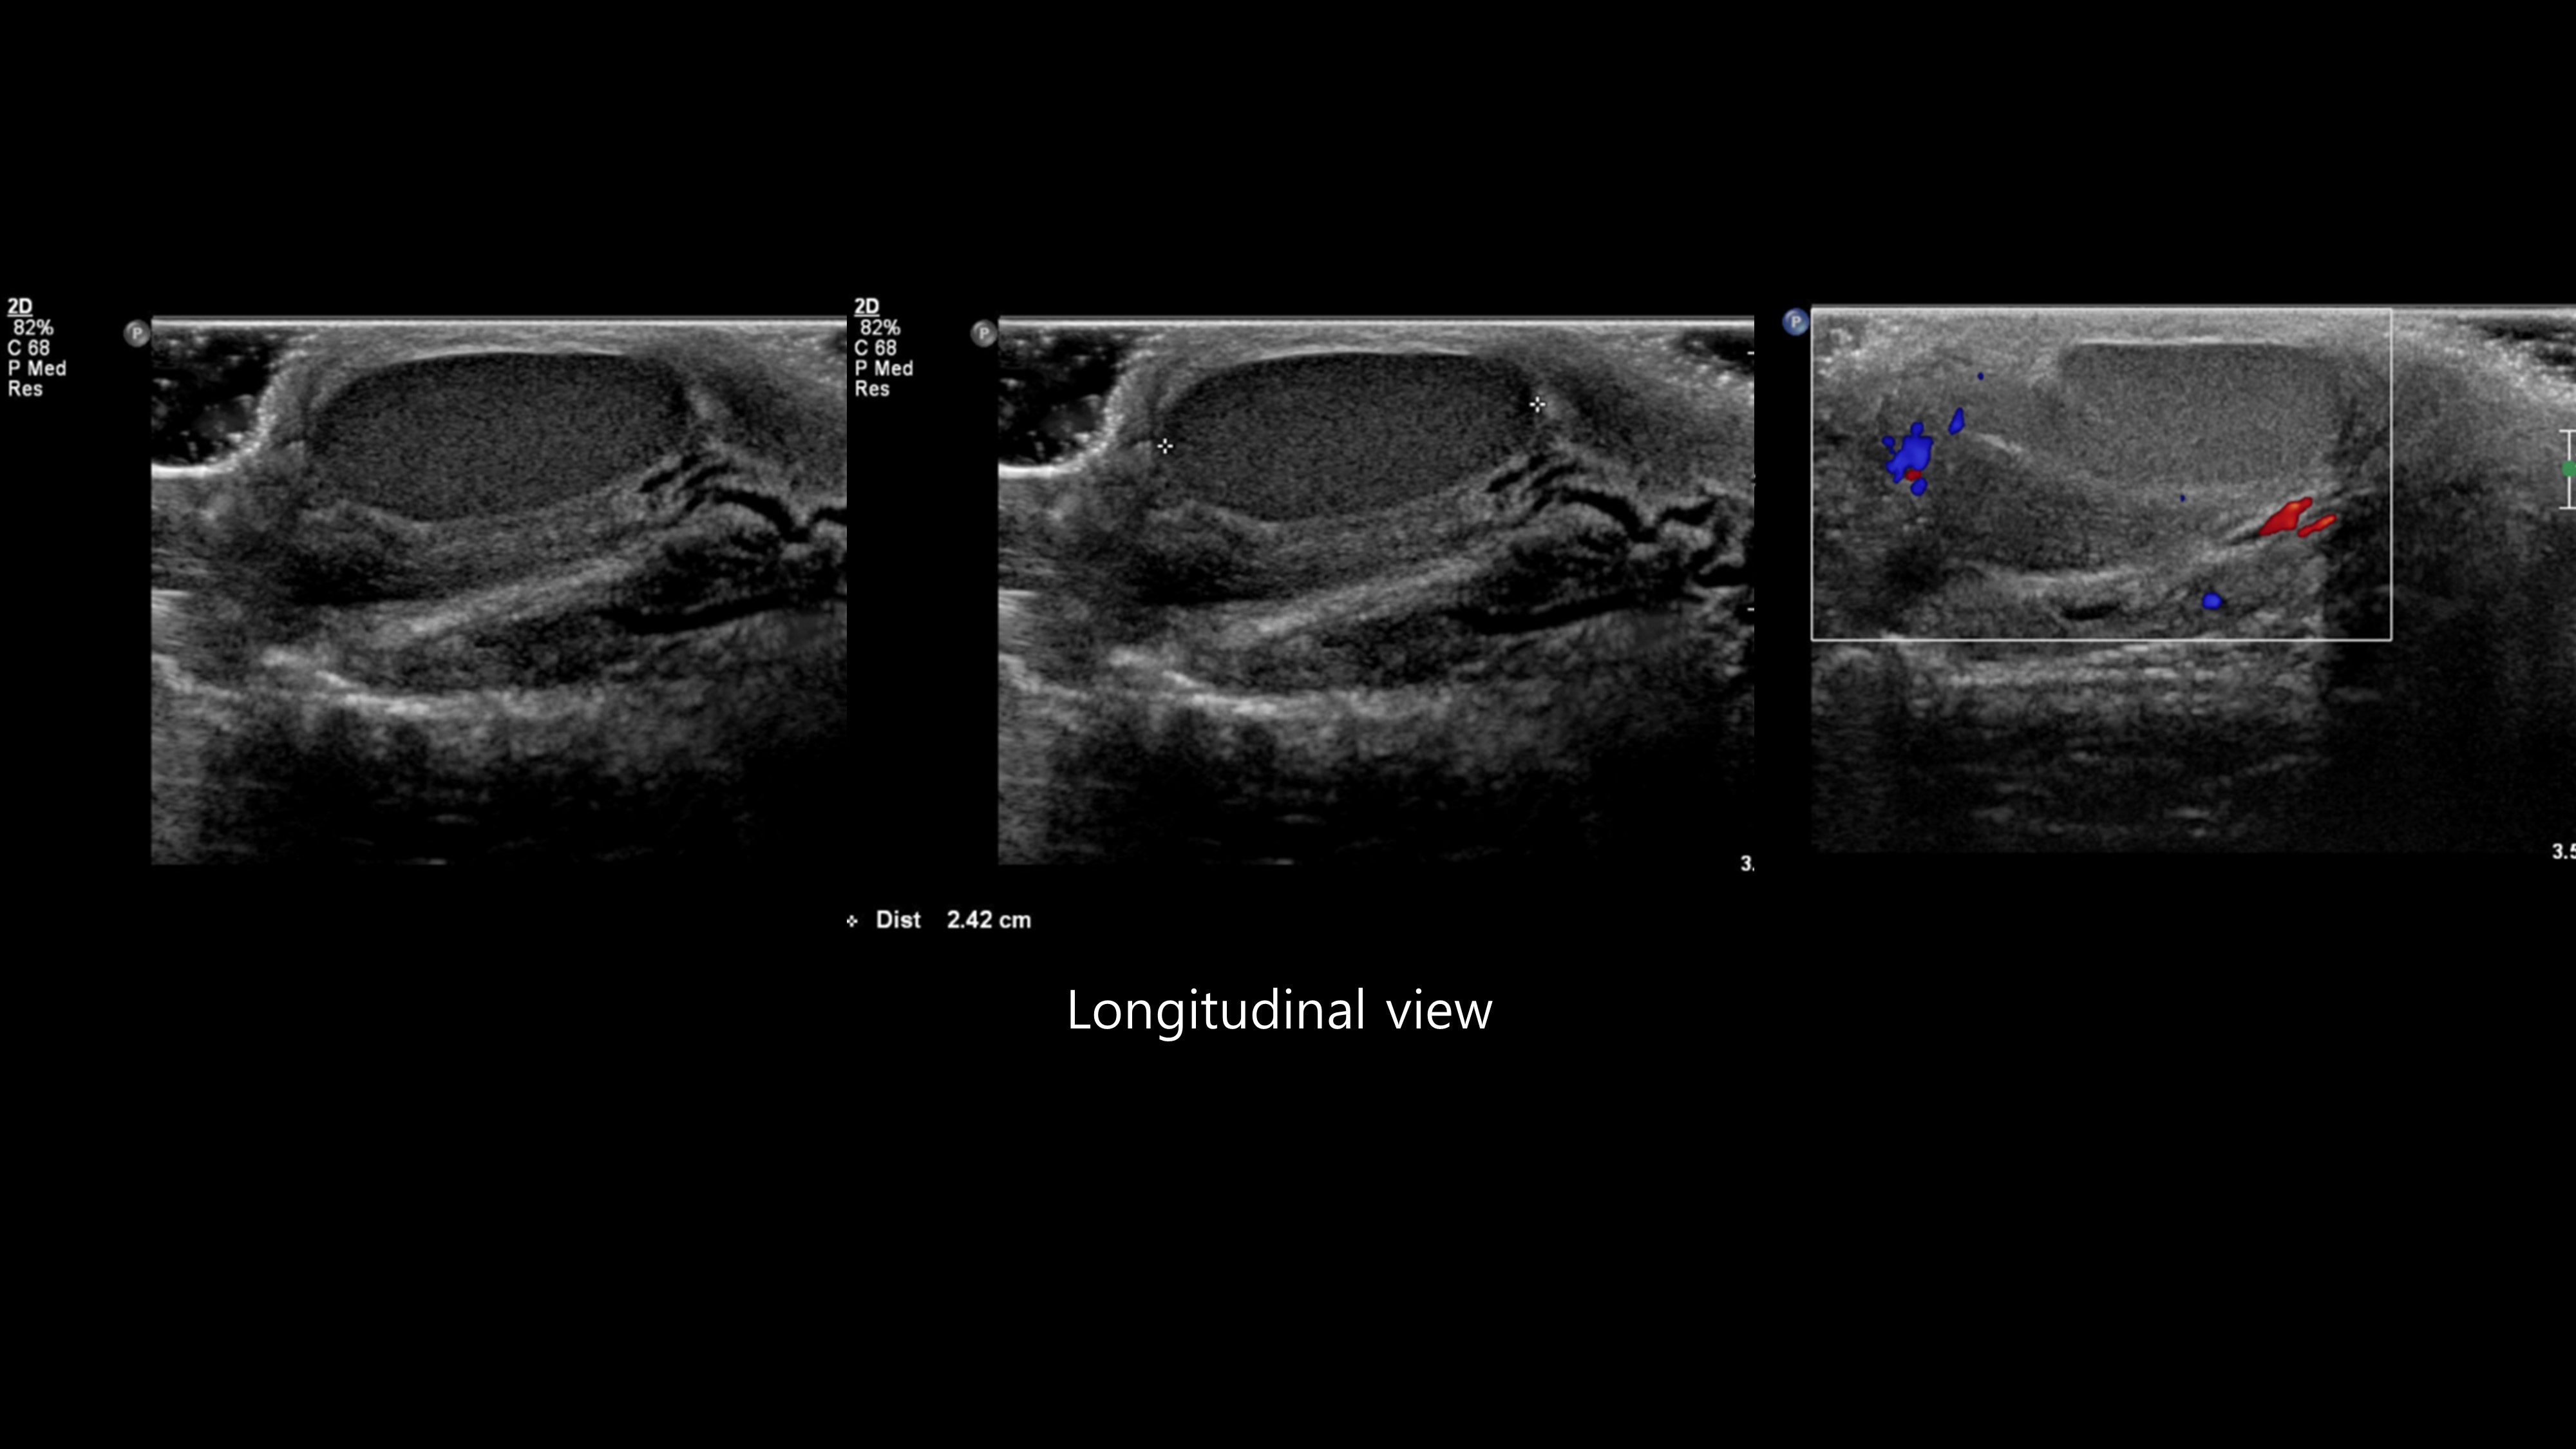

[350,Genitourinary [GU]] 18/M,Palpable penile mass

Genitourinary [GU]

US,

What is the best diagnosis?